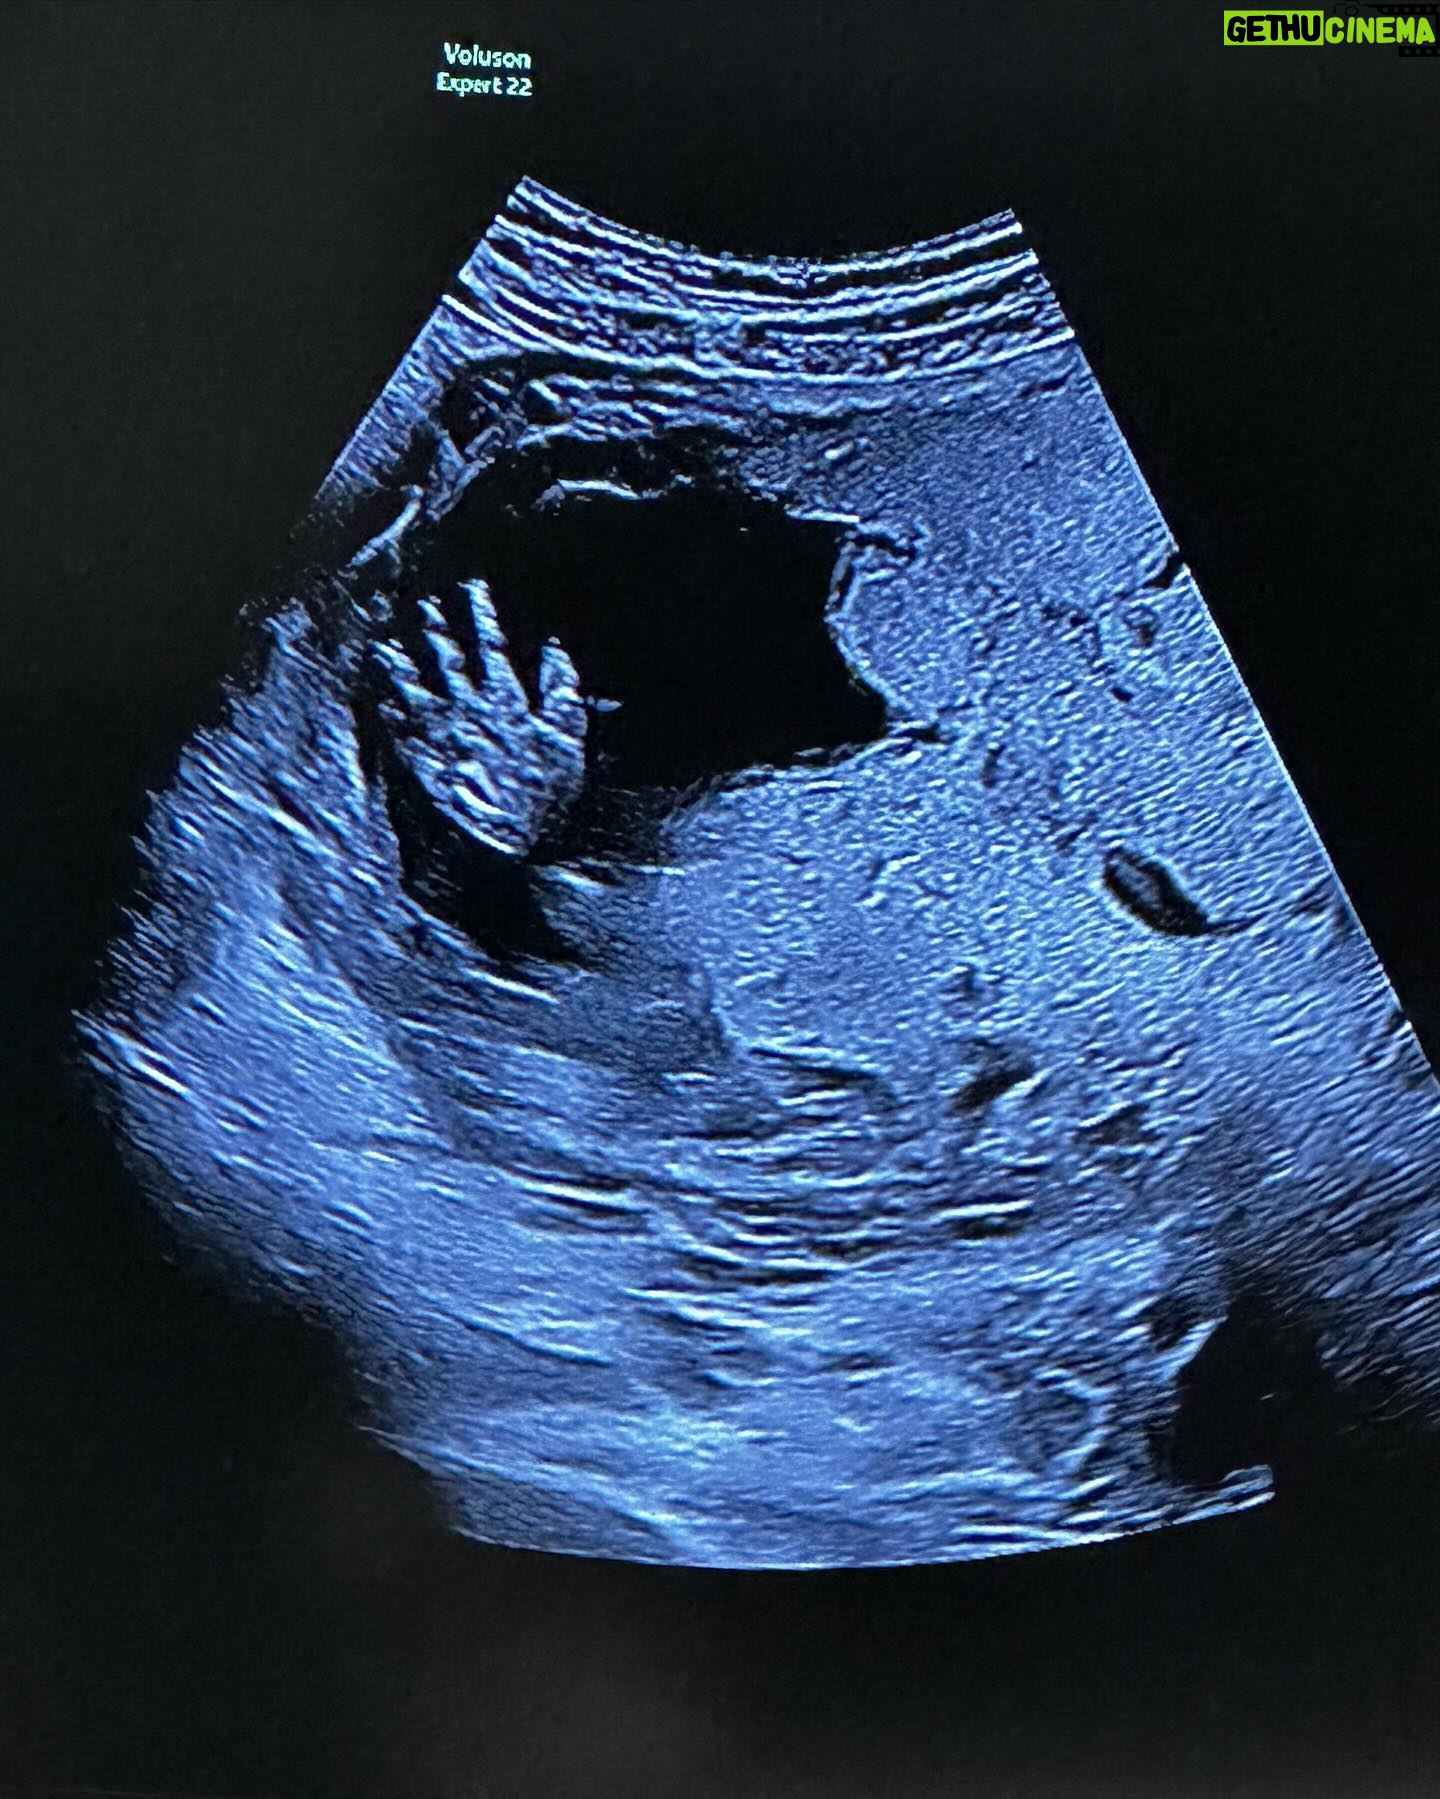

233.6K Likes – Caity Lotz Instagram

Caption : Gaining weight for the role of a lifetime 🤰🏼🥰 👋Likes : 233621

233.6K Likes – Caity Lotz Instagram

Caption : Gaining weight for the role of a lifetime 🤰🏼🥰 👋Likes : 233621

233.6K Likes – Caity Lotz Instagram

Caption : Gaining weight for the role of a lifetime 🤰🏼🥰 👋Likes : 233621

233.6K Likes – Caity Lotz Instagram

Caption : Gaining weight for the role of a lifetime 🤰🏼🥰 👋Likes : 233621

128.2K Likes – Caity Lotz Instagram

Caption : The bump is bumping. Pretty cool to be growing life inside my belly 😊 so excited to meet this new soul!Likes : 128238

128.2K Likes – Caity Lotz Instagram

Caption : The bump is bumping. Pretty cool to be growing life inside my belly 😊 so excited to meet this new soul!Likes : 128238

128.2K Likes – Caity Lotz Instagram

Caption : The bump is bumping. Pretty cool to be growing life inside my belly 😊 so excited to meet this new soul!Likes : 128238

Caption : Capturing one of the most special times of my life. 🩷 This is 30 weeks pregnant and my belly is already so much bigger. I’m excited, nervous, and already feel so much love for the life growing inside mi belly! Thank you to my talented friends for making it happen: 📸 @trickyrickyt 💄 @alisonc.muaLikes : 120786

120.8K Likes – Caity Lotz Instagram

Caption : Capturing one of the most special times of my life. 🩷 This is 30 weeks pregnant and my belly is already so much bigger. I’m excited, nervous, and already feel so much love for the life growing inside mi belly! Thank you to my talented friends for making it happen: 📸 @trickyrickyt 💄 @alisonc.muaLikes : 120786